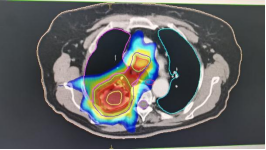

1、肺癌横断面及矢状面肿瘤处治疗剂量显示图

3、计划系统效果图:黄色线内-蓝色线外深颜色区域为高剂量区域,黄色线外及蓝色线内为低剂量区域。即照射剂量区域可按肿瘤治疗的需要进行调节。